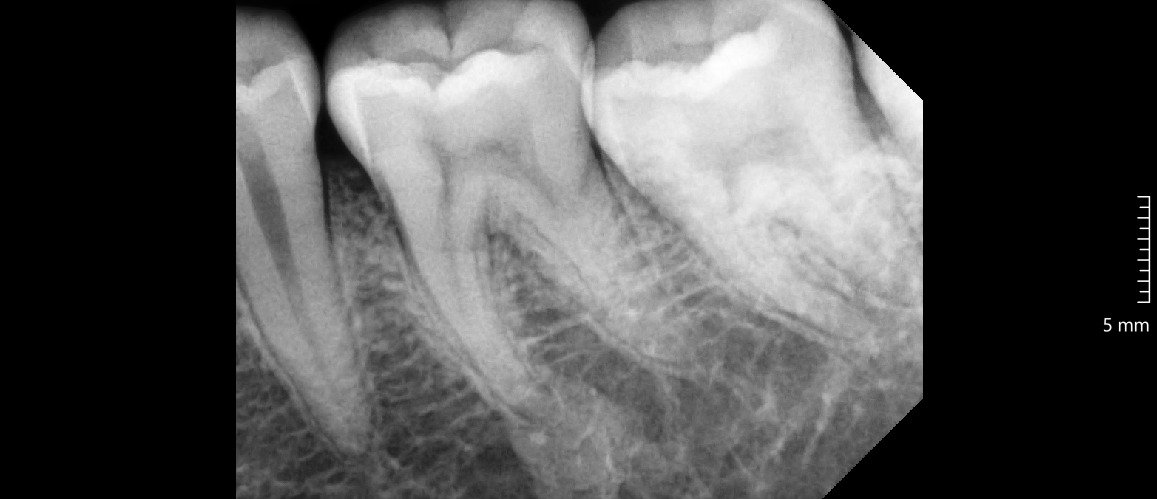

Dokter melakukan rontgen panoramic untuk melihat posisi gigi bungsu dan menilai kondisi pasien.

• Teknologi rontgen panoramic modern.